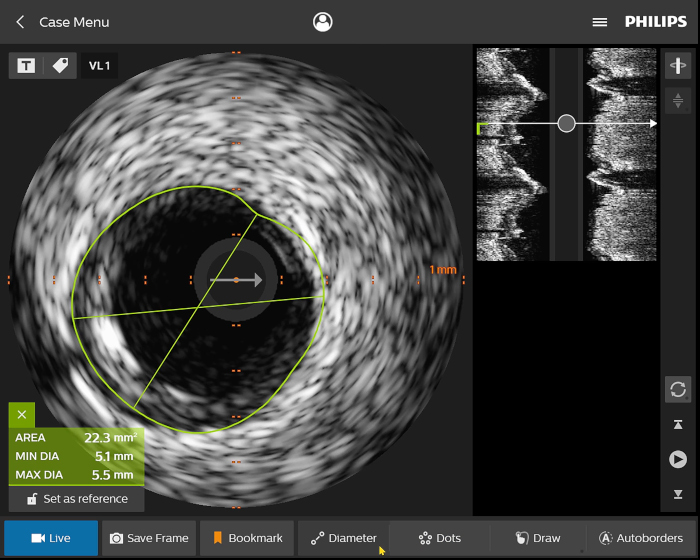

Presentamos la nueva plataforma de aplicaciones intervencionistas Philips IntraSight, en la que la imagen, la fisiología, el corregistro* y el software se unen para facilitar una atención óptima del paciente. IntraSight ofrece un conjunto completo de modalidades clínicamente probadas, como la iFR/FFR, la IVUS y el corregistro* para simplificar las intervenciones complejas, acelerar los procedimientos rutinarios y proporcionar una mejor atención al paciente.

Construida sobre una plataforma inteligente basada en aplicaciones que puede escalar para satisfacer las necesidades cambiantes de su laboratorio cuando se disponga de nuevas aplicaciones o modalidades, sin necesidad de adquirir nuevo hardware. Solo Philips IntraSight ofrece las mejores herramientas de imagenología y fisiología de su clase con iFR, corregistro iFR*, FFR, IVUS, corregistro IVUS* y Angio+*. Con su arquitectura modular, IntraSight se mantiene a la vanguardia de los últimos avances y actualizaciones de seguridad importantes.

Digital IVUS imaging